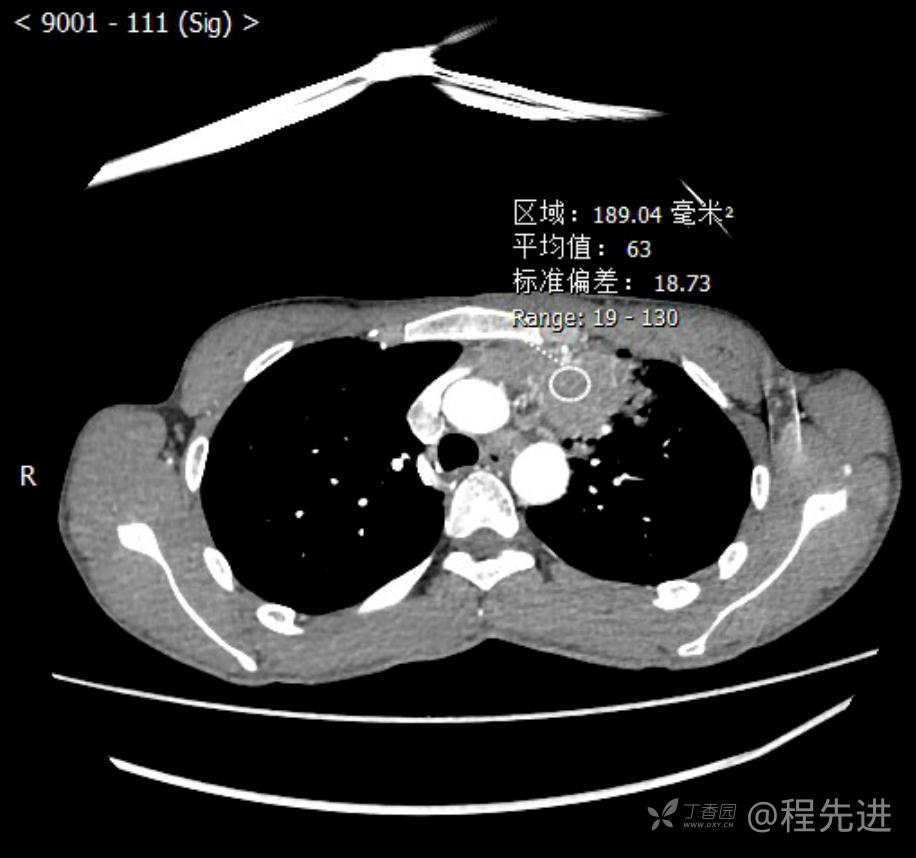

主诉:反复咳嗽1月,发现“纵隔”占位半月,乏力10余天。

现病史:患者1月前无明显诱因出现咳嗽,以夜间为著,伴有少量白痰,无发热,无胸痛、咯血,无痰中带血,未予重视,半月前外院行胸部CT检查发现“左前上纵隔”占位,未予进一步检查及治疗。近10余天自觉乏力,逐渐加重。